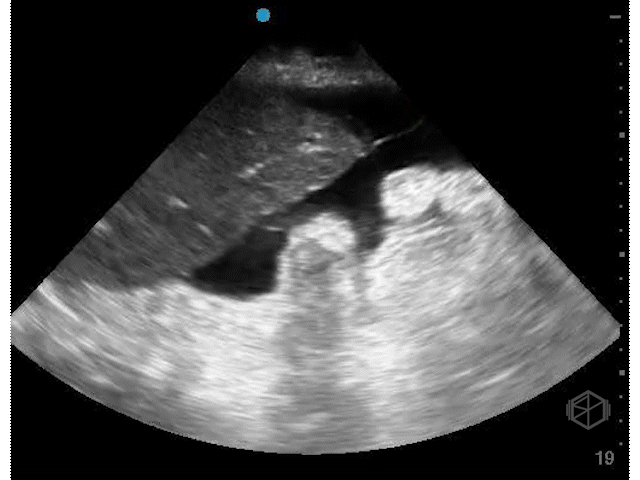

Several days later, she returned to the ED with hypotension, lightheadedness, and mild abdominal discomfort. Recognizing the potential urgency, Dr. Weinberger immediately performed a POCUS, which revealed the following:

The patient had complex free fluid in the abdomen, noted with septations and fibrinous stranding. Surgery was immediately notified and a CT was performed a little while later that showed a moderate amount of free air in the abdomen, fluid suspicious for peritonitis, and concern for a leak at the small bowel connection in the right lower quadrant. In surgery, cloudy bile-tinged fluid was found but no stool. The previous connection had poor blood flow and a small leak. That section was removed, a new connection was made between healthy bowel, and the abdomen was closed. The patient tolerated the procedure and did well.